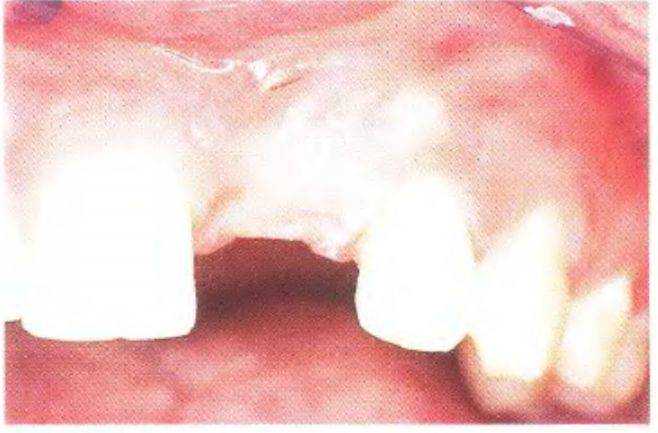

Рис. 3 39а. Пациентка 17 лет с отсутствующими латеральными резцами верхней челюсти

Съемный частичный протез с литым каркасом. Имеющийся протез не удовлетворял пациентку.